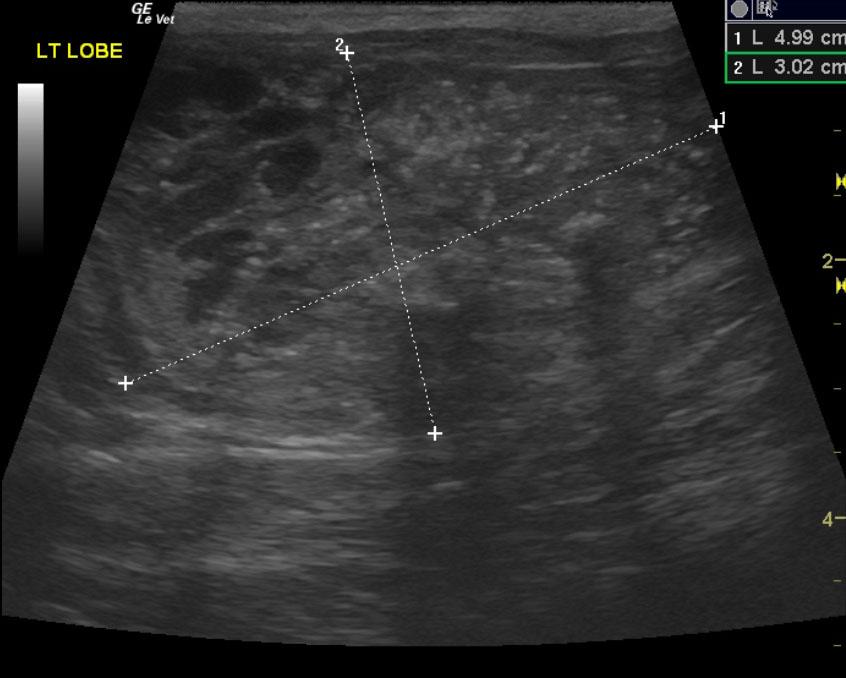

A 9-year-old male neutered Plotthound dog was presented for evaluation of polyuria, polydypsia, and occasional loose stool. Abnormalities on CBC and serum biochemistry included mild anemia, mild leukopenia, mildly increased ionized calcium, and mild azotemia. T4 was within reference range at 4.4.